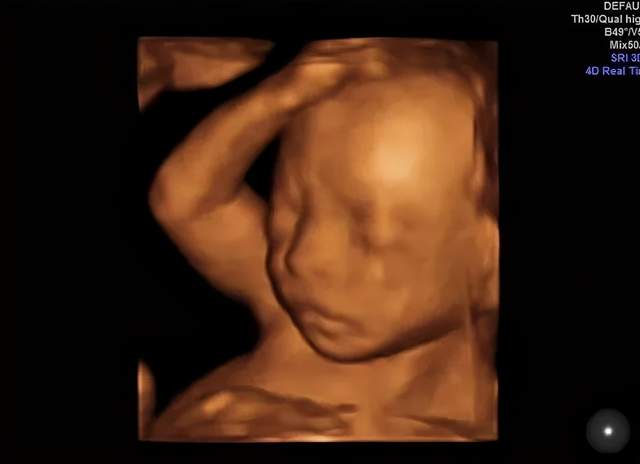

嗯,开始检查了!医生在妈妈肚子上涂了好多凉凉的东西,然后用一个小仪器在妈妈的肚子上探来探去。没多久,妈妈就看到了你的动态了哦!妈妈真的像在四维影院看电影一样的,看到你在肚子里各种欢腾的样子。

你看你爸爸,激动的一直说话,“老婆老婆!你看宝宝鼻梁多高,你看他还在吃手,你看他圆圆的脑袋好可爱啊……”宝贝,你爸爸是不是像个大孩子一样,看到你就手舞足蹈,语无伦次了。哈哈哈哈,你老爸让你一定要遗传他那活泼又搞笑的基因呢!

嘿嘿,下面照片就是你的“写真”,还是“裸体”的呢,不要害羞哈!这个可是爸爸妈妈送给你的礼物哦。等你长大了,看到在妈妈肚子里面的照片,是不是会很意外啊?嘿嘿,这个啊就是四维彩超的神奇功效啦,可以让爸爸妈妈看到你健健康康的成长,看到你欢快的动作还让爸爸妈妈稀里哗啦的留下了好多感动的眼泪呢。宝宝,爸爸妈妈等着你哦!

(转过来转过去,只为让医生和粑粑麻麻更清楚的看到我的盛世美颜)